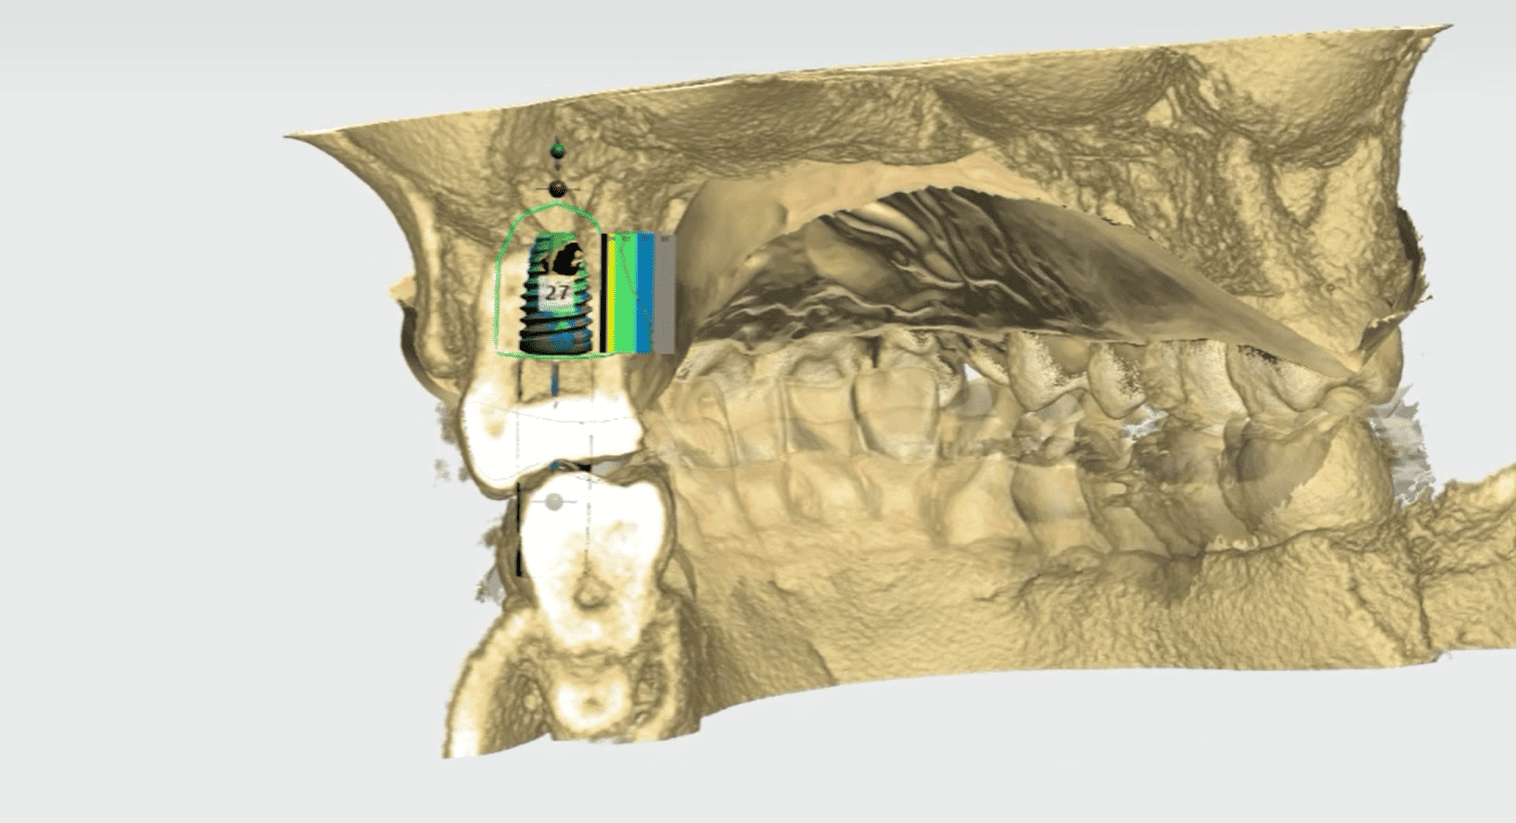

數位植牙是結合影像科技與電腦規劃的植牙方式,通常包含以下技術:

3D電腦斷層掃描(CBCT)

透過三維影像,醫師可以清楚看到:

.齒槽骨厚度

.神經位置

.植牙空間

電腦模擬植牙位置

在手術前先透過軟體模擬植體角度與位置,降低手術誤差。

.png)

客製化手術導引板

部分案例會製作導引板,協助醫師精準定位植體。

這些數位技術能讓植牙規劃更精準,也能幫助醫師提前預判風險。